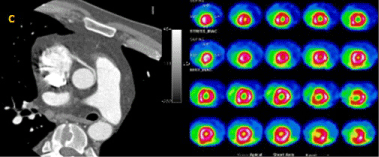

The second case was a 35-year-old man with chest pain at rest for five days, with normal biomarkers and a left bundle branch block on the ECG. CTA evidenced an anomalous origin of the RCA from the left sinus with an inter-arterial route between the aorta and the main pulmonary artery, with minor narrowing of the artery but a good distal calibre. Cardiac SPECT did not show any myocardial perfusion abnormality and no relationship was found between the coronary anomaly and clinical symptoms (Figure 3a and Figure 3b).

Figure 3: Diagnostic work-up of a patient with an anomalous origin of the right coronary artery (Case 2). A) Computed tomography angiography. The right coronary sinus, with an inter-arterial course B) Myocardial perfusion SPECT negative for ischemia. View Figure 3